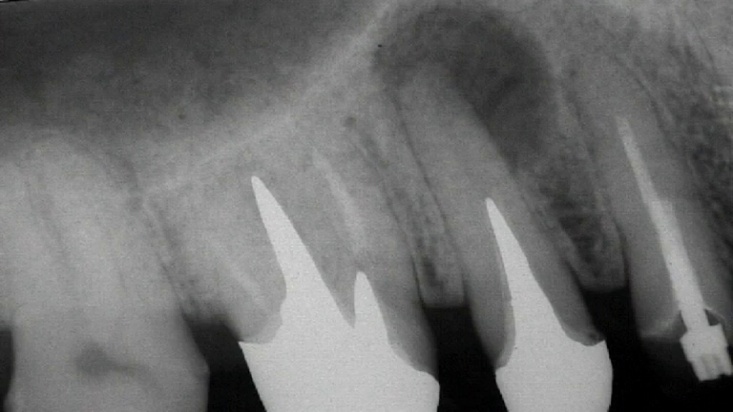

Сл. 37.69 а) Предоперативна радиографија. Два фрагмента од сребрен шилец се присутни во коренските канали. б, в) Сребрените шилци се отстрануваат со „Канцелиер“. г) Контролна радиографија по една година.